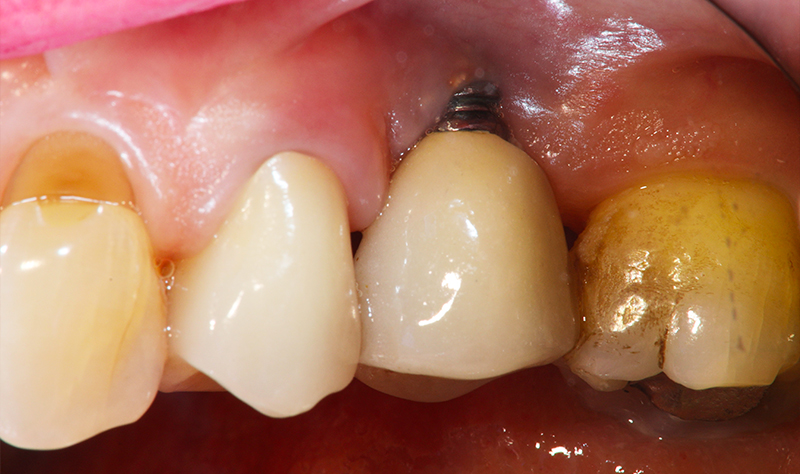

Dettaglio dell'elemento interessato da perimplantite

Fig. 2 - Dettaglio dell'elemento interessato da peri-implantite con evidente situazione clinica patologica.

Nell'ultimo anno le è stata riscontrata complicanza a carico dei tessuti peri-implantari di elemento zona 25. L'esame visivo e lo status fotografico (Figs. 1-2) evidenziano un’alterazione dello stato dei tessuti molli peri-implantari, che guida il clinico verso un’indagine più approfondita tramite acquisizione RX. Si esegue perciò esame radiografico del sito coinvolto (Fig. 3), da cui risulta un’importante riassorbimento osseo a carico dell’impianto. Si procede con sondaggio peri-implantare profondo, con la finalità di definire estensione e forma del difetto (Fig. 4) e, associandolo all’esame radiografico, di eseguire la conta delle spire implantari esposte. Tale manovra verrà effettuata con l’impiego di anestetico da irrigazione, data la nota dolorolabilità in peri-implantite, in quanto tale patologia determina la perdita di barriere connettivali e pertanto la penetrazione in osso durante il sondaggio.